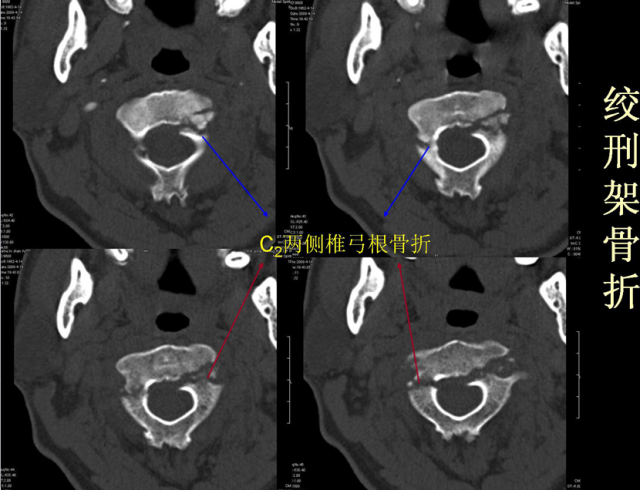

骨折篇

01

定义:骨折{Fracture}是指骨的完整性和连续性的折裂或粉碎。包括创伤性骨折、疲劳性骨折和病例理性骨折。 临床上以创伤性骨折*常见。